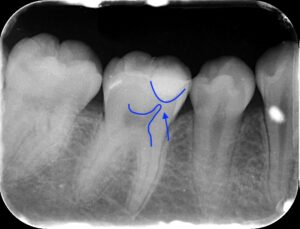

画像では下の飛び出た部分が神経で上の部分が虫歯で

非常に神経に近い虫歯となります。冷たいものや熱いものに

それほどしみず、また打診痛といって叩いても痛くない

のでMTAセメントの適応となり、MTAセメント療法を

行いました。

レントゲンではきれいにMTAセメントが埋まって

います。